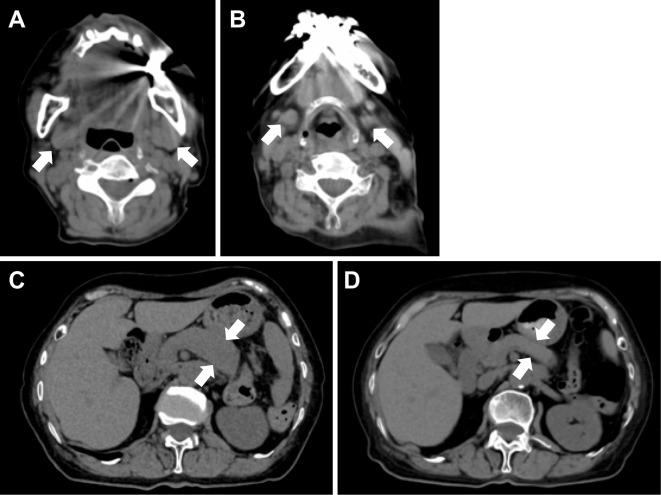

A 78-year-old Japanese woman with no history of rheumatic disease received 2 doses of the BNT162b2 COVID-19 mRNA vaccine. Two weeks later, she noticed bilateral swelling in the submandibular region. Blood tests showed hyper-immunoglobulin (Ig)G4emia, and F-fluorodeoxyglucose (FDG)-positron emission tomography (PET) revealed the strong accumulation of FDG in the enlarged pancreas. She was diagnosed with IgG4-related disease (IgG4-RD) according to the American College of Rheumatology (ACR)/the European League Against Rheumatism (EULAR) classification criteria. Treatment was started with prednisolone at 30 mg/day, and the organ enlargement improved. We herein report a case of IgG4-RD that may have been associated with an mRNA vaccine.

一位 78 岁的日本女性,既往无风湿病史,接种了两剂 BNT162b2 COVID-19 mRNA 疫苗。两周后,她注意到双侧下颌下区域肿胀。血液检查显示高免疫球蛋白(Ig)G4 血症,氟-18 脱氧葡萄糖(FDG)正电子发射断层扫描(PET)显示 FDG 在肿大的胰腺中强烈积聚。根据美国风湿病学会(ACR)/欧洲抗风湿病联盟(EULAR)分类标准,她被诊断为 IgG4 相关疾病(IgG4-RD)。开始用泼尼松龙 30 mg/天治疗,器官肿大得到改善。我们在此报告一例可能与 mRNA 疫苗相关的 IgG4-RD 病例。